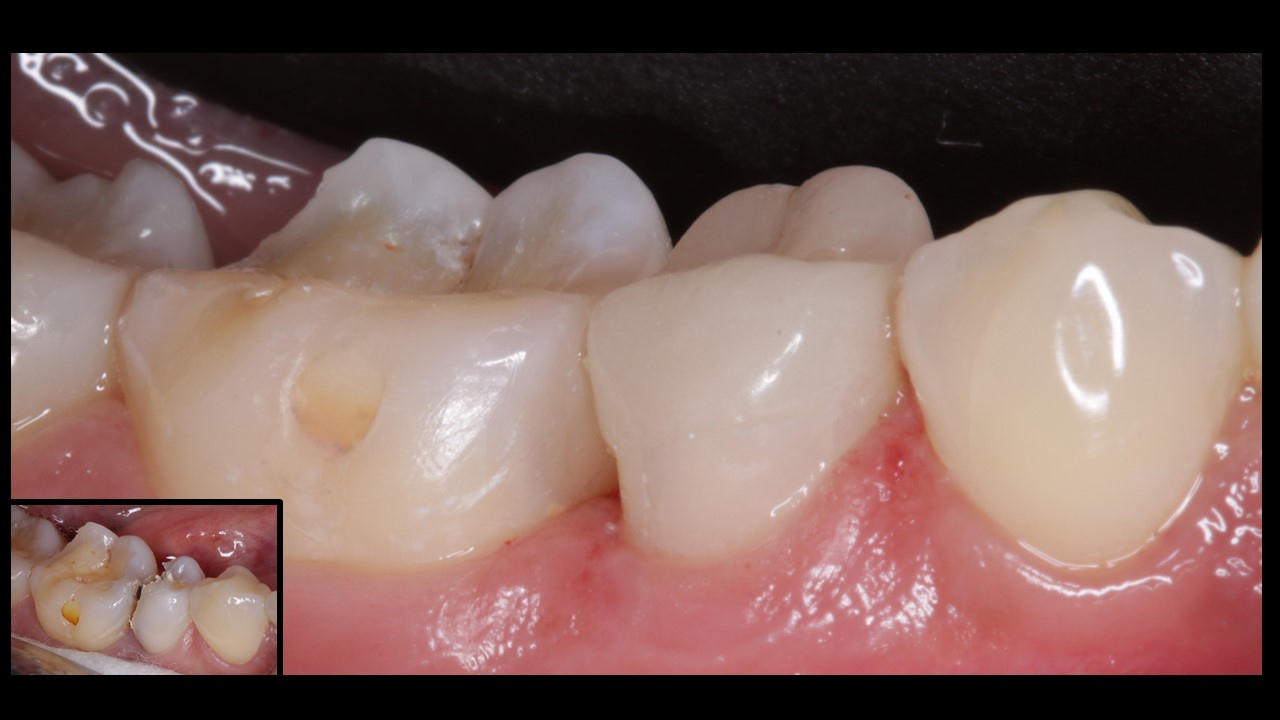

Patient presented with pain and discomfort in the lower right second premolar. Pain was of radiating type accompanied with food lodgement. On examination, the lower right 2nd premoalr was decayed with a portion of the distal surface lost due to the process of deacy. Examination alos revealed decay of the molar on the mesial side. Typical presentation that accompanies food lodgement and decay.

Incidentally the 1st molar on the left side was also decayed , with pulpal invovement requiring intervention.